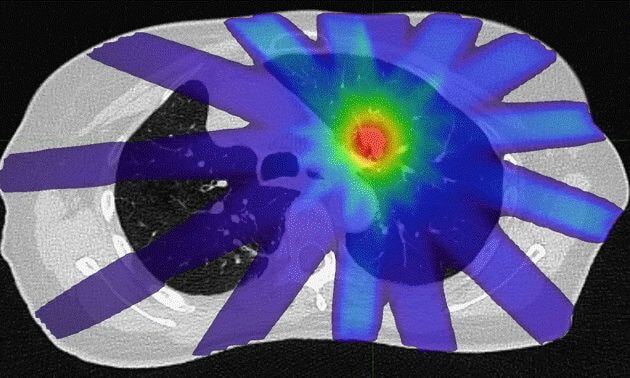

BRAVE-Lung

Robotergestützte bronchoskopische Radiofrequenzablation bei Lungenkrebs im Frühstadium - eine neuartige Krebstherapie

CCCZ Lighthouse Project

OMD-ZH

Oligometastasierung besser verstehen, gezielter behandeln

CCCZ Lighthouse Project